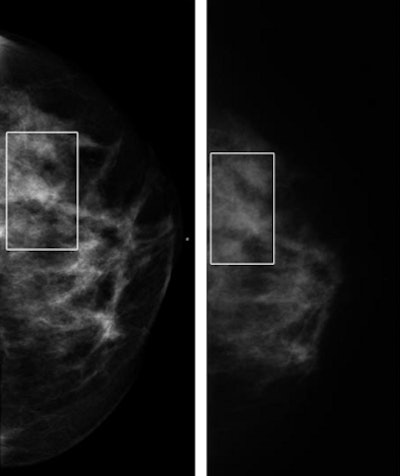

| Craniocaudal mammographic views of dense left breast in 52-year-old-woman. Full digital mammogram obtained by using Senographe system (above, left) and close-up view (below, left) of area outlined (in rectangle), as compared with full film-screen mammogram of same breast (above, right) and close-up view (below, right) of area outlined (in rectangle), reveal how improved contrast in dense part of the breast depicted on the digital mammogram enables visualization of the cancer, an invasive ductal carcinoma, on the digital image but not on the film-screen image. The lesion was not visible on either the mediolateral oblique film-screen or digital mammograms. |